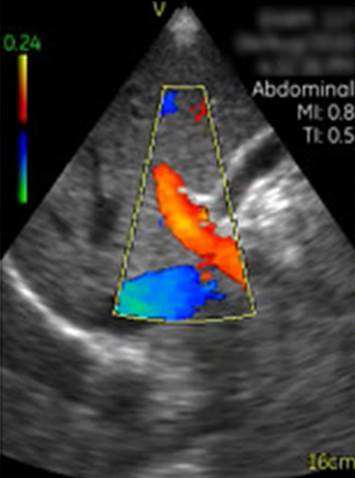

Vscan临床图片 腹部